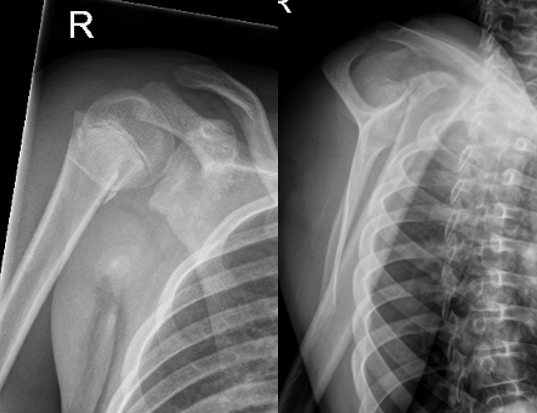

三,常见骨折移位形态:

近端骨折块:处于屈曲、外展并外旋位 (受肩袖肌群牵拉)

远端骨折块:向前内侧移位、短缩并内收 (受胸大肌、背阔肌、大圆肌牵拉)

必须拍摄肩胛骨Y位片以评估向前移位情况